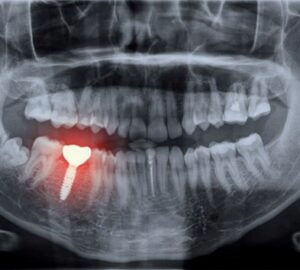

Here’s a real-world pattern seen often in Houston.

A patient gets a “budget” implant.

It works fine for a year or two.

Then bone loss starts.

The crown loosens.

An infection shows up.

Now the implant has to be removed, bone grafting is needed, healing takes months, and the replacement costs double or triple the original price.

That’s not affordable. That’s a delayed expense.

dental implants